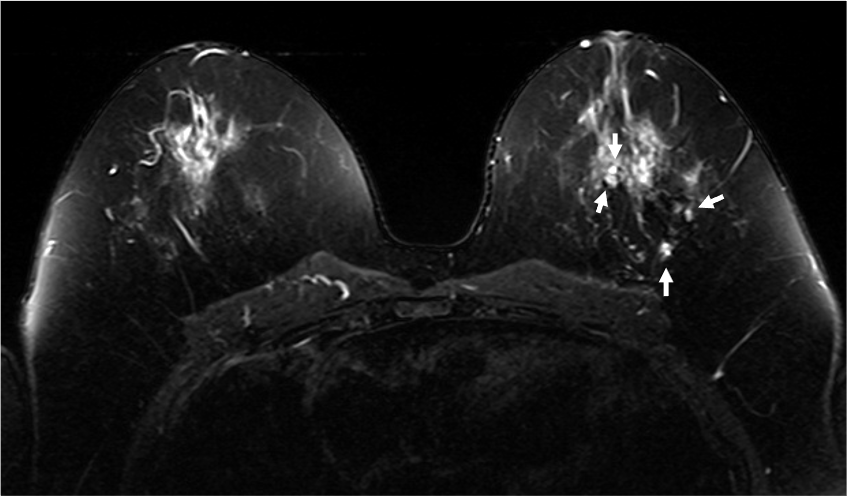

4. ダイナミックMRI (造影前 早期相 遅延相)

乳腺散在性の乳房であるが、造影早期から背景乳腺の大部分が造影されており、BPEはmarkedである。DCISの病変(矢印)は、clumped、segmental distributionの腫瘤非形成性病変(Non-mass enhancement)を示しているが、BPEが強く、広がり診断が困難である。